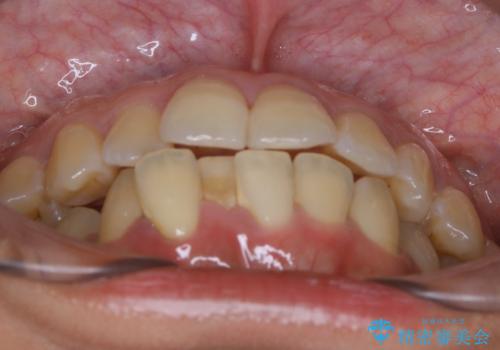

- 前歯を後ろへ下げることを主訴に来院された患者様です。

10代の時に非抜歯でワイヤー矯正をしていました。

口元の突出感の改善や歯の移動量などを考慮し、抜歯を伴うワイヤー矯正での治療を選択しました。

抜歯を行うことで前歯を後ろへ下げるスペースを獲得し、口元の突出感や歯のガタつきを改善していきました。